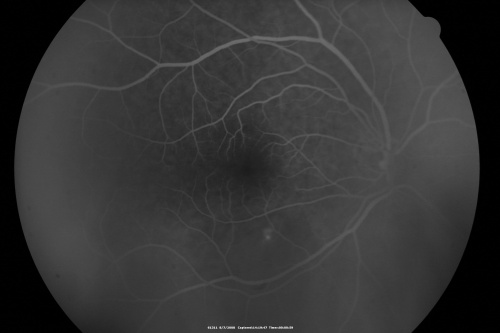

Idiopathic Central Serous Retinopathy - Bilateral - Acute

49-year-old man  decreasing vision in the left eye for one week.  He is not taking any steroid or steroid-related products.  His blood pressure as far as he knows is under control.

VISUAL ACUITY:  OD 20/30, OS 20/400